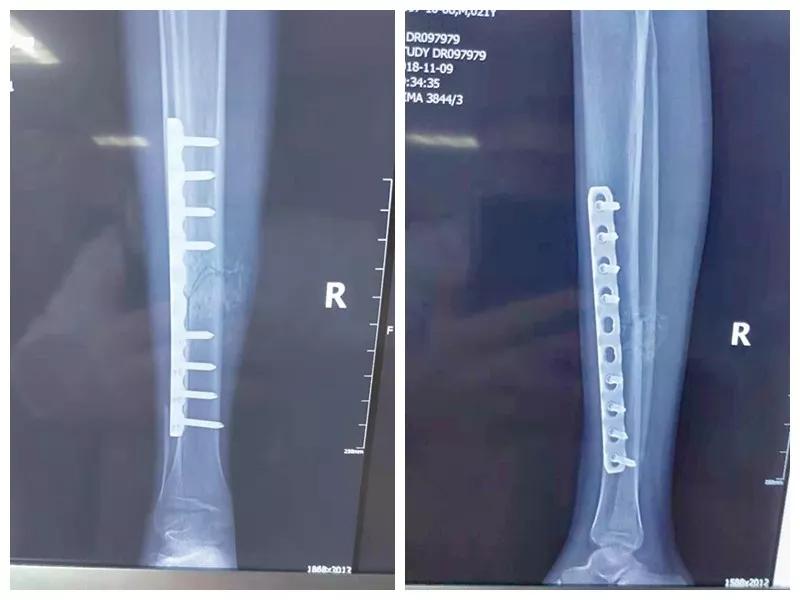

这名21岁的男性患者一个月前因车祸致伤,在当地某三甲21点游戏规则 确诊为右胫腓骨粉碎性骨折,骨折移位明显,建议手术治疗,因既往患严重慢性再生障碍性贫血病史16年,一般状况差,需长期输注血液制品维持三系细胞水平,麻醉及手术风险极高。虽经当地积极内科治疗,患者一般状况仍差,无法耐受手术治疗。患者及家属经多方打听,抱着最后一丝希望来到我院骨二科求治。

骨二科张延平主任接诊后经仔细询问病史,详细阅读近期X线、CT等病历资料,认为患者骨折移位明显,目前骨折无任何愈合迹象,若保守治疗,骨折将无法愈合,后期不能下地活动,严重影响患者生活质量。同时患者合并慢性再障,血常规结果各项指标均极低,围术期发生麻醉意外、大出血、感染等风险极高;而我院作为西安市级最大的三甲综合21点游戏规则 ,综合实力深厚,既往相关疾病治疗经验丰富,多次通过多学科诊治为合并复杂内科疾病患者保驾护航,为患者创造手术时机,提高患者生活质量,遂将患者收住院。住院后,立即成立了由张延平主任、杨寅副主任、山卉护士长、梁晨主治医师、刘邦定主治医师、李鑫护师组成的手术治疗小组。经初步检查,患者血常规结果较当地检验结果更差,三系细胞均极低,其中血小板仅为1(正常值为100-300),血红蛋白55g/L。遂立即请血研所李罡灿主任医师会诊,给予升高白细胞、纠正贫血、升高血小板等治疗,经积极治疗患者血常规各项指标均较入院时改善。张延平主任再次组织由血研所李罡灿主任医师、麻醉科崔晓岗主任、感染科付建军主任、药剂科韩小年副主任药师等参加的术前讨论。讨论后一致认为患者目前各项指标虽然较入院时改善,但因其慢性再障病史长,骨髓造血及储备能力极差,围术期发生大出血、伤口感染甚至全身感染等风险仍极高,术中及术后需准备大量血小板防止大出血,同时需高度警惕手术切口、取骨区术后发生感染。为尽快为患者施行手术,治疗小组积极联系输血科为患者备血,并为患者制定了围术期抗感染方案;在我院输血科存血量严重不足的状态时,输血科张养民主任亲自联系市中心血站为患者准备手术中及术后所需的血小板制品。手术小组为患者制定了周密的手术方案及风险预案,10月31日,在麻醉科王永宏副主任医师、手术室高洁、赵耀护师的配合下,为患者施行了右胫骨粉碎性骨折切开复位、髂骨取骨植骨内固定术,手术历时70分钟,安全返回病房。术后患者渗血多,1周内连续每日平均渗血超过100ml,并出现发烧,最高39℃,复查血常规三系细胞较术前再次明显降低。李罡灿主任医师、付建军主任、韩小年副主任药师多次来科会诊,及时调整患者的治疗方案,输血科再次为患者的救治提供了强有力的支援和保障。在山卉护士长带领的护理团队精心护理下,患者未发生压疮等卧床并发症。目前该患者术后恢复良好,已出院进行下一步康复治疗。